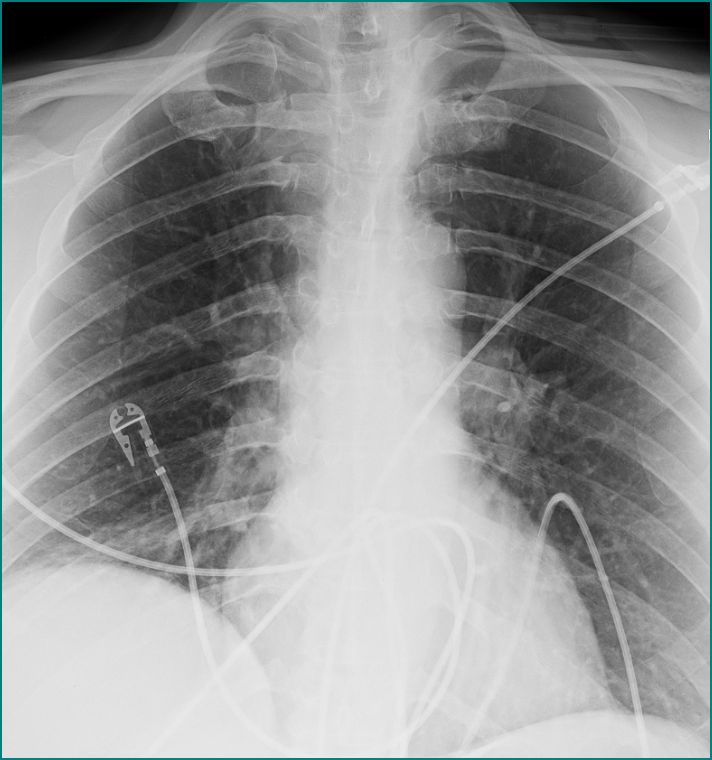

CHESTDRAINING METHODS Chest tube, Medical knowledge, Respiratory Meaning Of Chest High Water It can result from pneumonia,. Pleural effusion occurs when fluid builds up in the space between the lung and the chest wall. A pleural effusion is a buildup of fluid between the layers of tissue that line the lungs and chest cavity. A main cause of pulmonary edema is congestive heart failure. Pulmonary edema is a buildup of fluid in. Meaning Of Chest High Water.